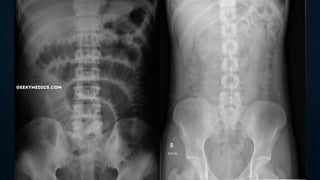

This document provides an overview of x-rays for medical students, covering topics such as ensuring x-rays are well-aligned, exposure levels, common artifacts and anatomical features, abdominal x-ray positions and views, and specialized x-rays including barium swallows, enemas, and tests to examine the esophagus, small bowel, biliary tree, and kidneys.